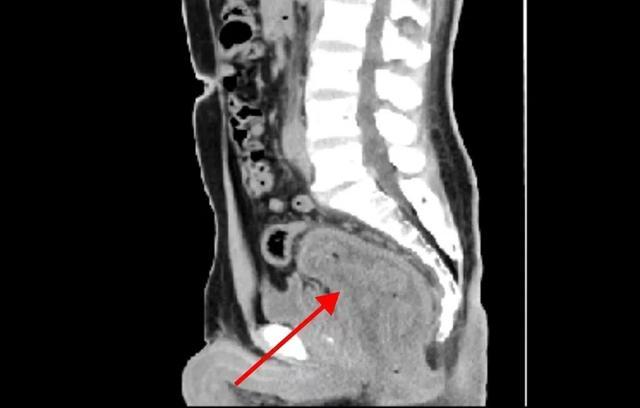

50岁的黄先生,因反复肛门肿块脱出30余年来汉寿县人民医院求诊。普外科二病区主任张晋维副主任医师团队经检查发现,肛门脱出物为直肠全层,有8cm长,完善辅助检查后诊断:直肠脱垂(重度)。科室团队结合患者病史、专科检查、年龄及身体状况等多方面因素,开展讨论评估并与患者家属充分沟通后,制定了Altemeier手术方案。

(患者术前影像学资料)

张晋维主任带领科室团队,在麻醉科的配合下,为患者行全麻下经会阴直肠乙状结肠部分切除术+盆底重建术+肛提肌加固术+乙状结肠肛管吻合术。经过2小时的精细操作,手术顺利完成,术中切除冗长脱出的直肠乙状结肠10cm,成功解除患者30年病痛之苦。术后经过精心管理,患者恢复良好,痊愈出院。